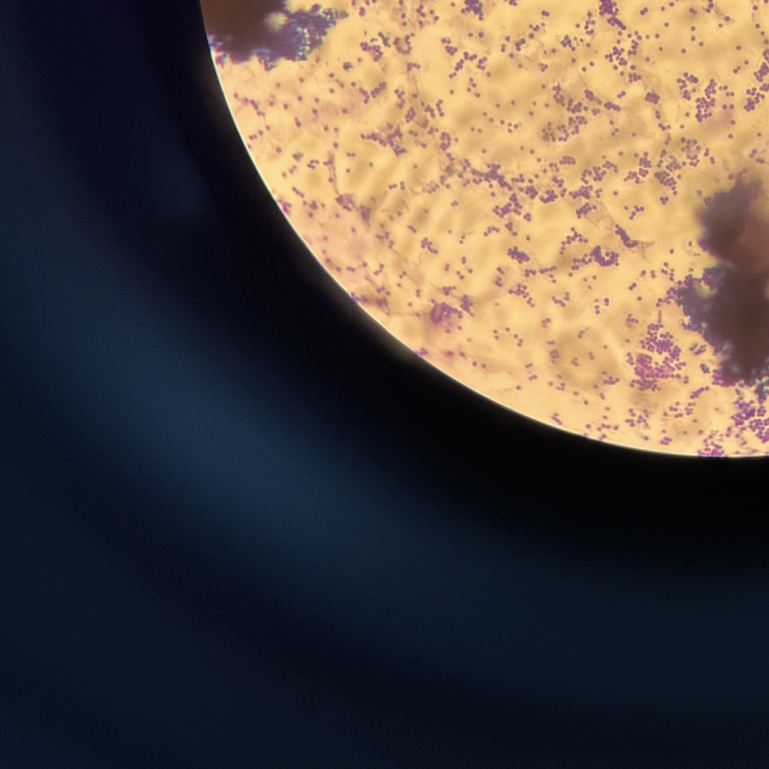

【检查】:额头,颜面可见多个米粒至绿豆大红色或肤色丘疹,粉刺,散在米粒大色沉斑。伍德灯下未见异常荧光。

【临床诊断】:痤疮